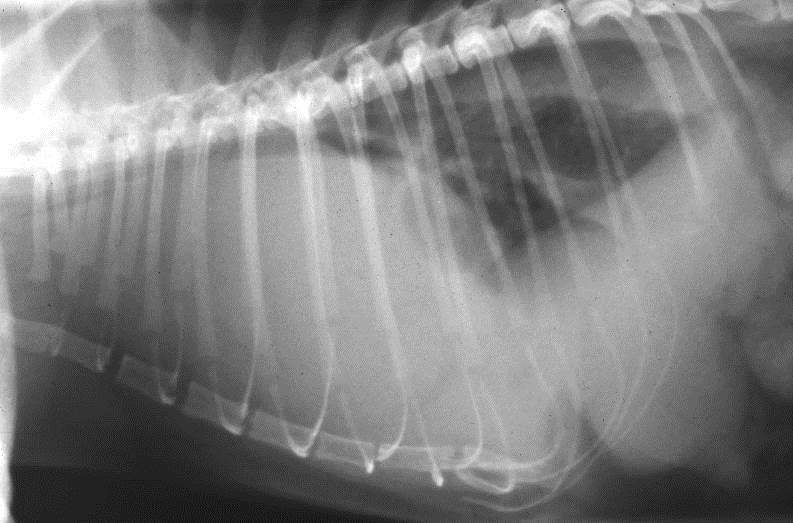

Look at this barium swallow of a dog?

Normal appearance of dog oesophogram